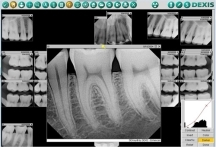

تصوير الأشعة السينية أثناء الحمل :

تُعد تصوير الأشعة السينية للأسنان جزءاً من الفحوصات الدورية، ولكن إن لم تكن ضرورية، يمكن تأجيلها لما بعد الولادة.

أما في الحالات الطارئة، فيمكن إجراء الأشعة بطمأنينة، لأن الجرعة المستخدمة لتصويرالأسنان منخفضة جداً ولا تؤثر على الجنين، خاصةً مع استخدام الدرع الرصاصي الواقي.

بحسب توصيات الكلية الأمريكية للأشعة، لا تحتوي أي أشعة سينية على جرعة إشعاعية كافية لإحداث ضرر على الجنين. ومع ذلك، تأثير الأشعة على الحامل في الشهر الأول حتى الشهر الثالث غير محبب عند الأطباء لان هذه المرحلة التي تتشكل فيها أعضاء الجنين الأساسية.